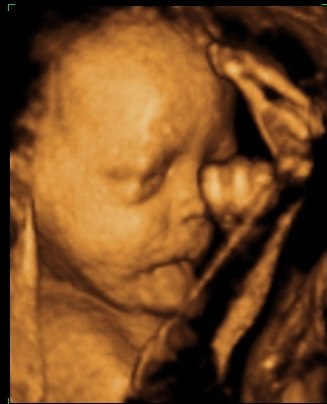

så var vi til 3D scanning i fredags. Så vild en oplevelse.. Hun er bare helt perfekt.

hun vejede 1423g, og så var hun en uge foran så det var da super dejligt at vide at lille pigen har det super og lever luxus derinde i maven

vi var heldige med at hun var rigtig aktiv plus vi også så hende med åbne øjne

Vedhæftede fotos (klik for at se i fuld størrelse)